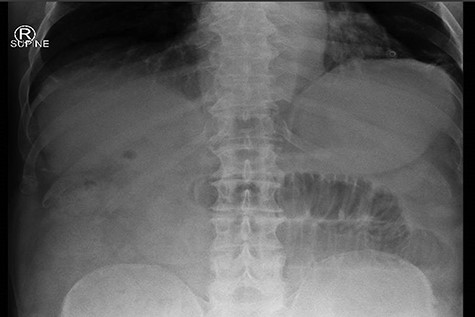

Given that the patient was clinically well, he was managed conservatively overnight with a nasogastric tube and intravenous fluid therapy. The CT scan was closely reviewed by the surgical team the following day and noted the presence of gas within the gallbladder, which was not commented upon by the radiologist (Fig. 2). Furthermore, SBO transition point appeared to be in the distal ileum, where a 3-cm “soft tissue” mass was seen (Fig. 3). His previous CT scan that diagnosed his chronic cholecystitis demonstrated a 3-cm gallstone within the gallbladder, which was not seen on the current CT. The findings of gas within the gallbladder in the setting of SBO and a mass of similar size to the known gallstone raised the suspicion for gallstone ileus. The patient then underwent a laparotomy and enterotomy for a 43-mm gallstone impacted in the distal ileum (Fig. 4). Apart from an episode of ileus, he made a full recovery post-operatively and was discharged home, with an outpatient follow-up in the surgical clinic.